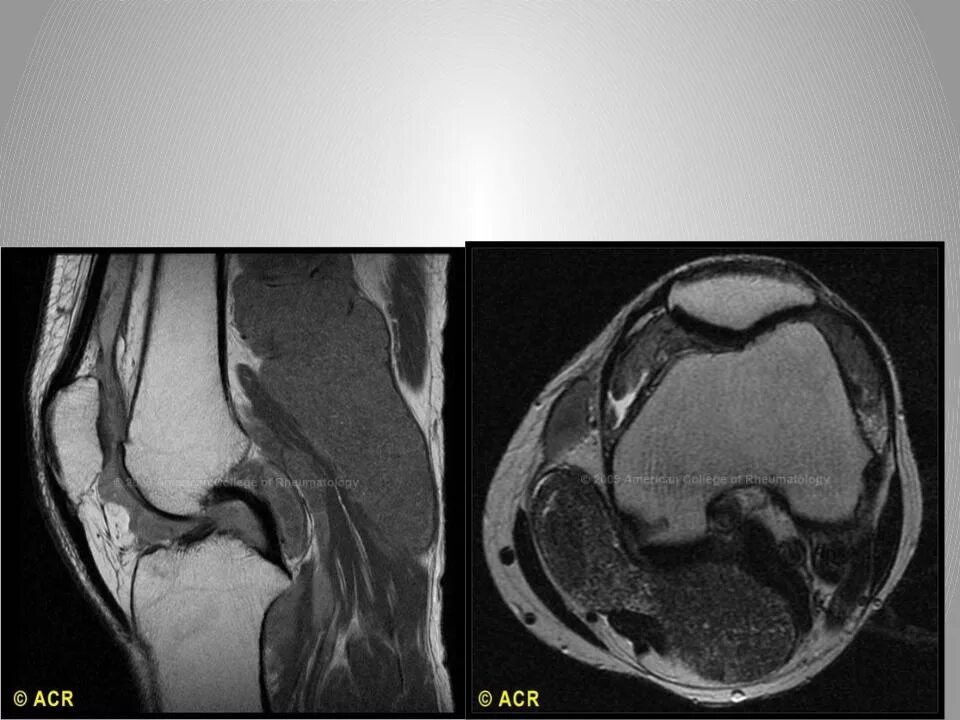

Мрт при боли в суставах